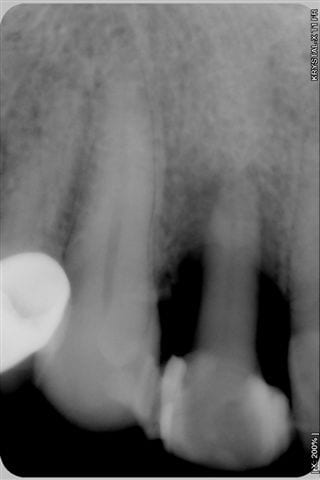

cas d'un patient arrivé vendredi en urgence, volumineux abcès vestibulaire sans fistulisation, au sondage poche de 8 mm en proximal: mésiale et distale, gencive attachée en vestibulaire,mobilité 3 pas le temps de prendre des photos, mais simplement une radio.

patient revu le 25 aout pour biostimulation, 4ème radio prise lors de la séance montre un début de régénération osseuse.

et voilà le résultat en radio lors des recalls du patient pour biostimulation:

patient revu le 25 aout pour biostimulation,2ème radio prise lors de la séance et qui montre un début de régénération osseuse.

La 3ème radio prise ce jour avec biostimulation en post op, montre que la régénération, que beaucoup d'entre vous pensait impossible, est bien entrain de se faire.

1-Le temps entre 1ere et 3e radio

2-Les radio ne semblent pas très standardisées au niveau des contrastes. La 1ere est très foncée, donc le défaut osseux peut sembler plus grave et la 3e est pâle, ce qui montre plus d'os. Ou bien je me trompe...

Net différentiel de contraste et/ou exposition entre la 3ème et les deux premières, non?

première radio le 22/07 et la 3ème aujourd'hui

Je me demandais ce qui pourrait encore vous faire douter, bingo "la première radio est plus sombre que la 3ème" eh bien en voici une prise le 22/7 en urgence et moins sombre, aurez vous encore des doutes quant au bien fondé d'un traitement conservateur laser assisté???